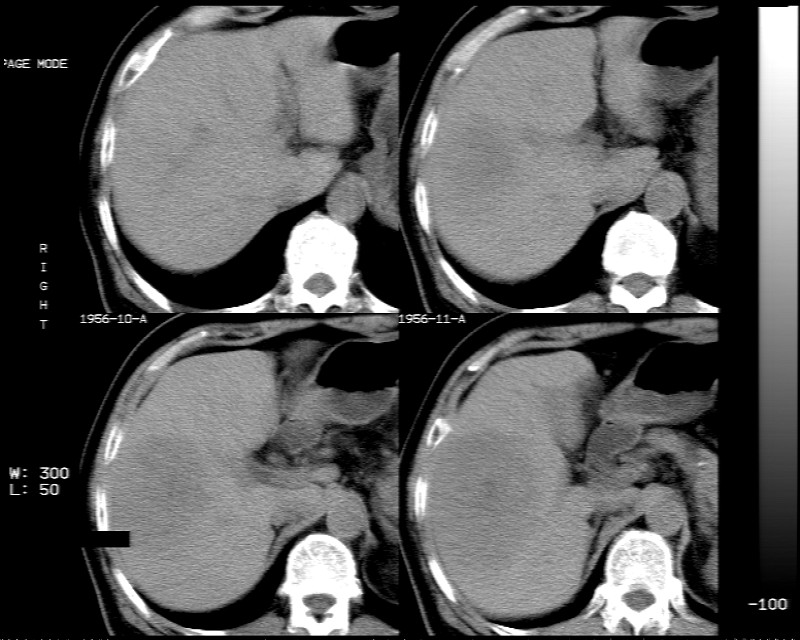

男 73岁 b超检肝右叶占位病变,afp阴性. 随访中.

肝脏右叶块状低密度影,增强后动脉期明显强化,门脉期强化减低,延迟期病灶又成低密度。考虑肝细胞癌。我认为比较典型。

低密度肿块,动脉期明显强化,可见星状低强化区,门脉期强化向中心扩展,但病灶动脉期强化最明显,门脉期及平延迟期强化减低,结合病只考虑巨大局灶性结节增生,血管瘤不除外

肝右叶巨大占位性病变,平扫呈低密度改变,增强扫描动脉期病灶周围强化,门脉期强化未退出,延时期病灶周边强化与肝实质接近,病灶中心在各期均可见星状不强化区;首先考虑局灶性结节增生可能性大,其次为血管瘤。肝癌不能完全排外(不首先考虑肝癌是因为强化不支持快进快出特点)。

平扫示:肝右后叶下段内见类圆形略低密度占位病灶,边界尚清楚,最大径约为102×71mm,ct值31~41hu。

动态增强扫描示:动脉期病灶显著不均性强化,病灶强化密度高于肝实质;平衡期病灶呈等密度;延迟扫描病灶密度略低于肝实质;三期均见占位病灶内有裂隙状无强化影。肝内胆管无扩张,腹膜后未见肿大淋巴结。

拟诊:肝右后叶下段内占位性病变,考虑为肝结节样增生。

建议进一步检查(mri/或穿刺活检),不排外肝ca。